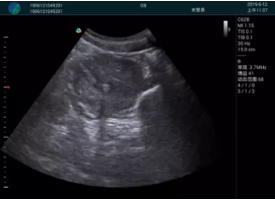

肝內(nèi)血管顯示清晰,血流敏感無外溢